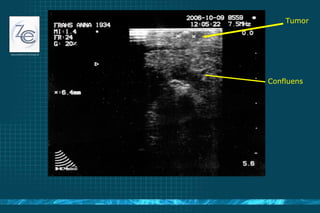

Tumor Confluens

Pankreas V.Lienalis Confluens